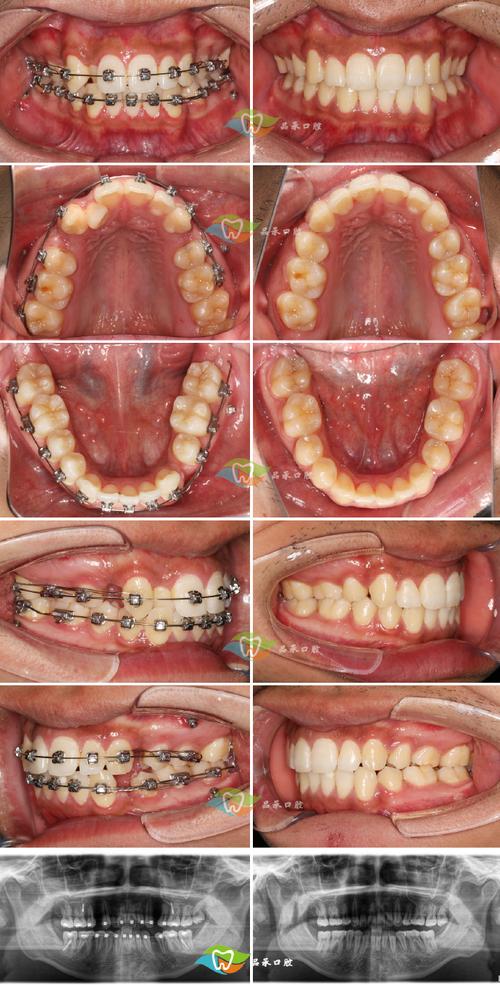

正畸治疗中拔牙是常见的调整方式,而“拔不对称的牙”则是个体化方案中的特殊设计,并非随意为之,这种拔牙方式需基于严格的口腔检查、面部对称性分析及咬合功能评估,目的是解决单侧牙齿拥挤、中线偏斜、牙弓不对称等问题,最终实现面部与口腔功能的平衡,以下从拔牙原因、设计原则、治疗流程及注意事项等方面展开详细说明。

正畸拔牙的核心目标是“为牙齿移动创造空间,协调牙量与骨量”,而不对称拔牙则针对更复杂的口腔问题,常见原因包括:

若患者一侧牙弓因骨量不足或牙量过大出现明显拥挤(如牙齿重叠、扭转),而另一侧相对整齐,仅通过磨牙或扩弓无法解决时,需在拥挤侧拔牙,为内收牙齿提供空间,左侧上下颌前磨牙区拥挤严重,右侧排列正常,可能选择拔除左上、左下第一前磨牙,利用拔牙间隙调整左侧牙弓形态,避免强行扩弓导致牙龈萎缩或面部凹陷。

面部中线是美学与功能的重要参考,若患者因乳牙早失、不良习惯(如偏侧咀嚼)导致上下颌中线不一致(如下牙中线右偏,上牙中线左偏),需通过拔牙调整,右侧后牙早失导致右侧牙弓塌陷,左侧后牙过度萌出,可能拔除左侧上颌第二前磨牙,配合右侧修复或压低左侧牙齿,纠正中线偏斜。

部分患者存在先天牙数异常(如一侧多生牙、先天缺失牙)或牙体严重病变(如一侧磨牙大面积龋坏无法保留),需拔除病变或多余牙,对侧保留健康牙,通过正畸移动恢复牙弓连续性,左侧上颌多生牙导致牙弓形态异常,右侧下颌第一磨牙无法保留,需拔除左侧多生牙及右侧下颌第一磨牙,利用间隙调整两侧牙齿位置。

对于轻度骨骼性不对称(如下颌偏斜),可通过拔牙进行代偿治疗,下颌左偏导致左侧后牙反颌,右侧后牙覆盖过大,可能拔除右上颌第一前磨牙及左下颌第二前磨牙,通过移动牙齿改善咬合关系,代偿骨骼不对称对面部美观的影响。